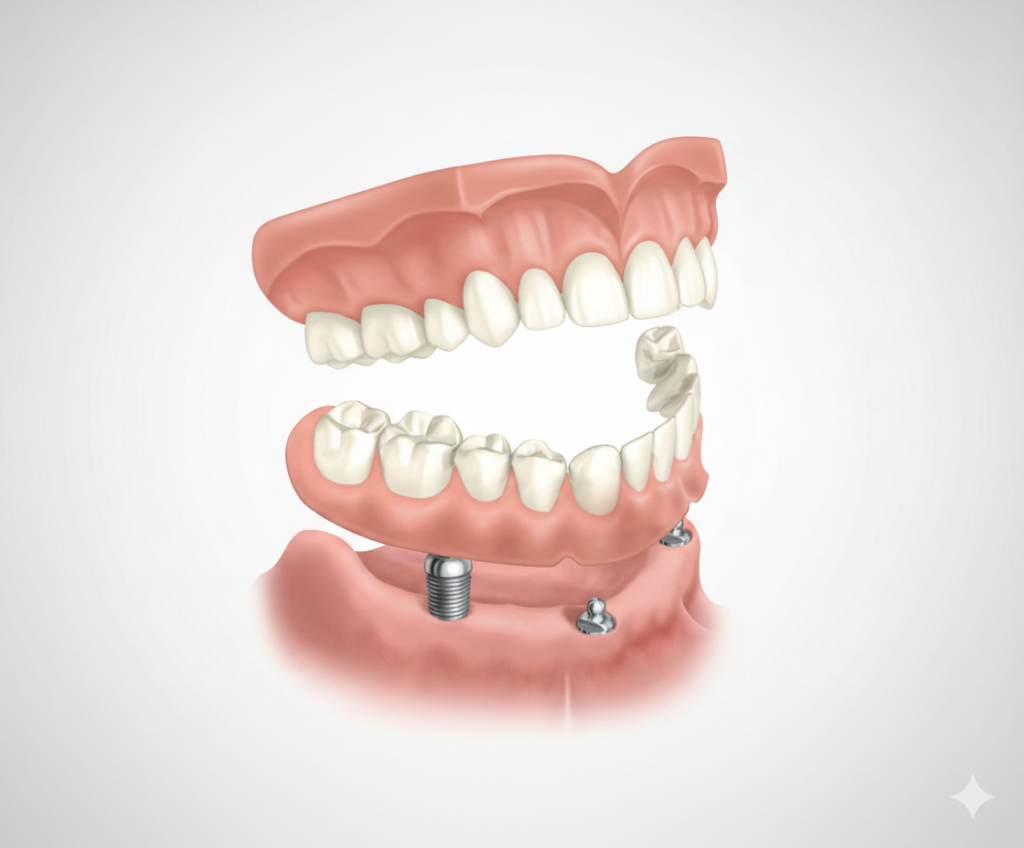

Herausnehmbarer Zahnersatz

Moderne herausnehmbare Zahnprothesen bieten Ihnen eine zuverlässige und ästhetische Lösung, um Ihre Lebensqualität und ein natürliches Lächeln im Alltag zurückzugewinnen. Dank präziser Anpassung genießen Sie einen hohen Tragekomfort und die Sicherheit, jederzeit unbeschwert essen und sprechen zu können.